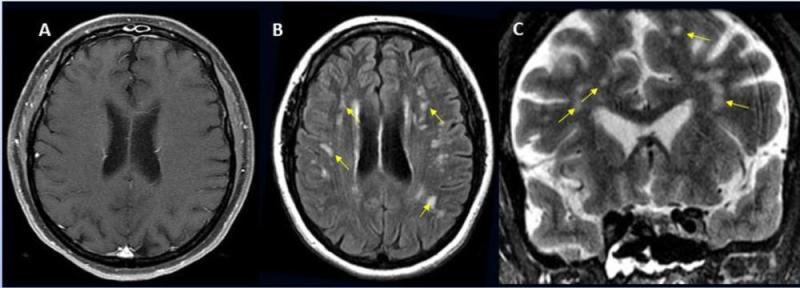

Significant alterations in the brain’s white matter in adolescents with ASD. Image courtesy of RSNA

-

Stroke seen in a 41-year-old male patient with COVID-19 infection. Image courtesy of RSNA

Acute anterior cerebral artery/middle cerebral artery watershed infarction seen in a 47-year-old male patient who presented with COVID-19 pneumonia. Image courtesy of RSNA

A 62-year-old male with a past medical history of hypertension presenting with seizures. Image courtesy of RSNA

A 56-year-old male patient with diabetes and hypertension who presented with complaints of confusion. Courtesy of RSNA

A 49-year-old female with past medical history of mitral valve disease and tricuspid valve regurgitation who developed headache followed by cough and fever presented to the ER with right upper eyelid ptosis (drooping). Courtesy of RSNA

Hemorrhage seen in 56-year-old female with COVID-19 infection and no other significant past medical history. Courtesy of RSNA

A 65-year-old male smoker, presented with acute hypoxic respiratory failure secondary to COVID-19 pneumonia, requiring intubation. Courtesy of RSNA